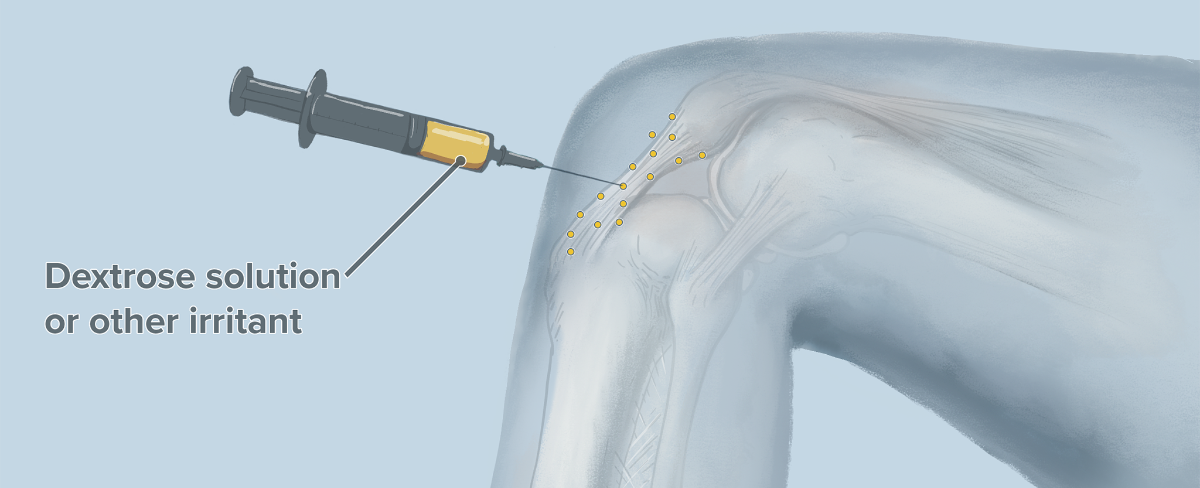

پرولوتراپی آرتروز زانو چیست؟

پرولوتراپی یا «تکثیر درمانی» روشی مبتنی بر تزریق است که در مشکلات مزمن اسکلتی عضلانی و ارتوپدی استفاده میشود. در این روش محلول هایی مانند دکستروز یا سرم نمکی به داخل مفصل یا تاندون تزریق میشوند تا با تحریک ترمیم بافت، درد کاهش یابد و عملکرد زانو بهبود پیدا کند.

پرولوتراپی استئوآرتریت زانو درمانی موثر بوده و موجب کاهش درد زانو می گردد. برخی مطالعات علمی تاثیر آن را مانند تزریق ژل داخل زانو می دانند.